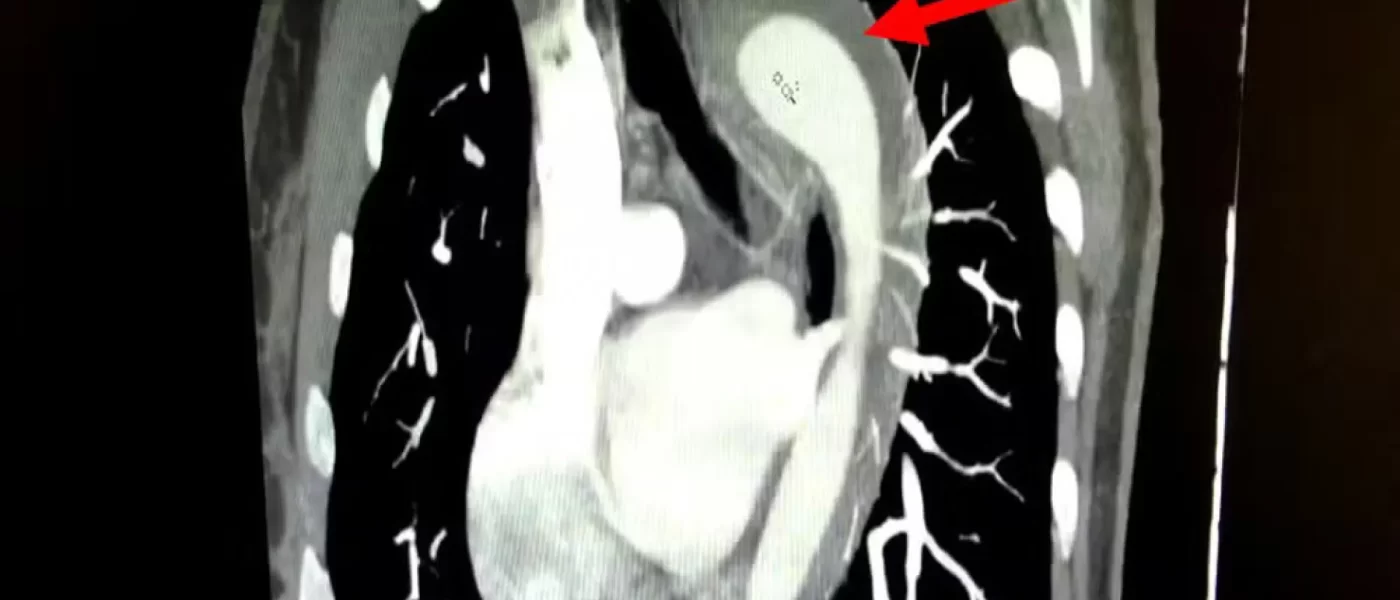

Mulher de 45 anos rompe aorta durante orgasmo e passa por cirurgia

Um caso raro e de alto risco envolvendo a ruptura da aorta foi relatado pelo American Journal of Case Reports. A paciente, uma mulher de 45 anos, d…